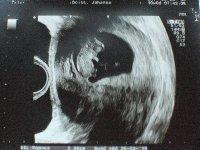

Hallo ihr Ich will heute auch mal Bildchen zeigen,weil ich jetzt doch sehr erleichtert bin, das doch alles in Ordnung ist. Es waren ja am Anfang noch 2 Fruchthöhlen da, mittlerweile hat sich unser Einzelkämpfer durchgesetzt und ist zeitgerecht entwickelt, schon 3 cm groß. Ich bin so froh das alles OK ist. Ich wünsch euch allen das es genauso gut aussieht. Nächster Termin ist in 4 Wochen. Liebe Grüße Johanna

Bild zu Auch mal Bildchen zeigen will :-) - Forum für März - Mamis